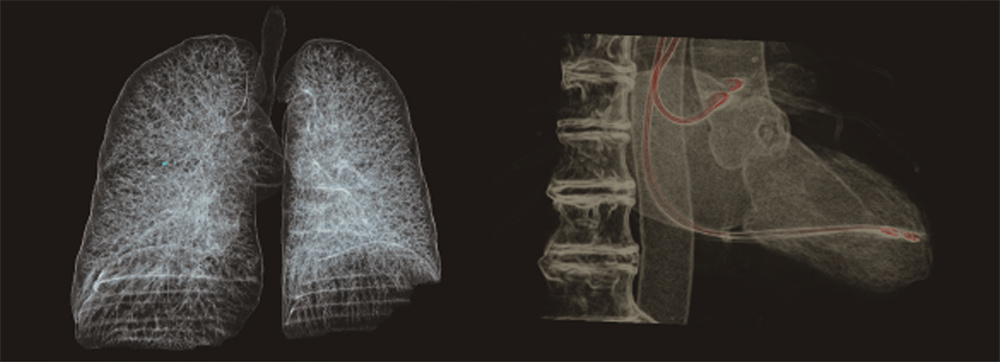

联影640层CT是中国CT届的“天花板”,集当今CT领域的顶尖科技于一身,将各项临床应用发挥到极致,为患者带来精准、舒适、安全的CT检查新体验。建立了心血管、神经、肿瘤、呼吸系统、泌尿系统及骨科专业等疾病的成像和低剂量筛查领域全新标准,真正实现全方位成像,结合AI人工智能技术,提高疾病诊断率。

采用液态金属轴承技术的超大热容量球管,结合独有的低千伏、低毫安成像模式,联影640层CT可实现肺部、冠脉等全身各部位大扫描通量、微辐射剂量的体检筛查。?